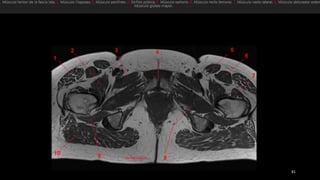

• Glúteo mayor (GMa)

• Glúteo medio (GMe)

• Glúteo menor (GMi)

• Fascia lata (FL)

• Tendón del glúteo menor (1)

• Aanterior del tendón del glúteo

medio (2)

• Posterior del tendón del glúteo

medio (3)

• TM, trocánter mayor

• Tm, trocánter menor.

• Glúteo mayor(GMa) • Glúteo medio (GMe) • Glúteo menor (GMi) • Fascia lata (FL) • Tendón del glúteo menor (1) • Aanterior del tendón del glúteo medio (2) • Posterior del tendón del glúteo medio (3) • TM, trocánter mayor • Tm, trocánter menor.